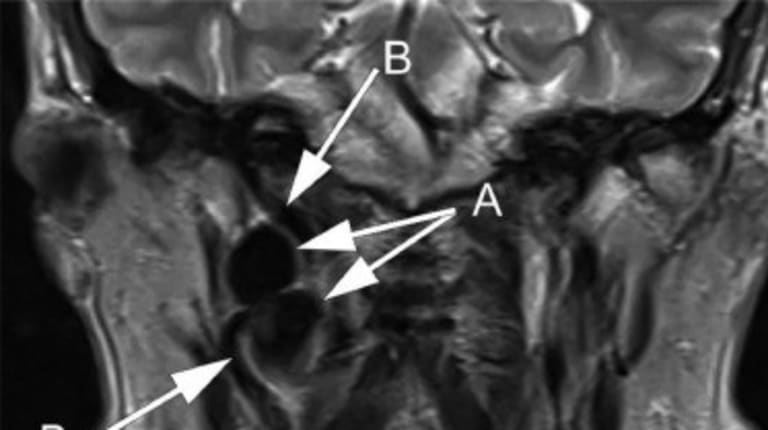

Ein 66-jähriger Mann stellt sich mit seit 5 Monaten bestehenden intermittierenden, stechenden Schmerzen im rechten Kiefer und Hals vor, die bis zum Ohr ausstrahlen und sich beim Kauen und Schlucken verschlimmern. Die klinische Untersuchung ist unauffällig, eine Glossopharyngeusneuralgie wird diagnostiziert. Die Ursache bleibt zunächst unklar.

MRT-Aufnahme des Halses des Patienten.